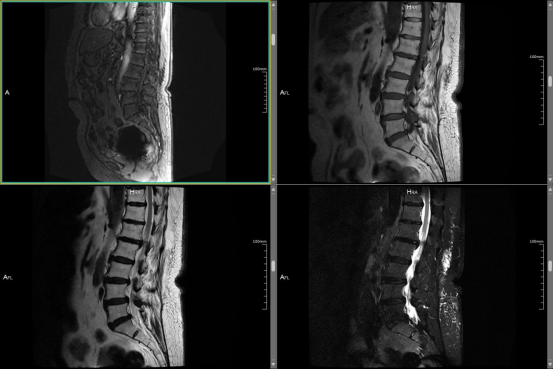

【医声守护·科普】第234期:有避孕环可以做腰椎核磁共振吗?